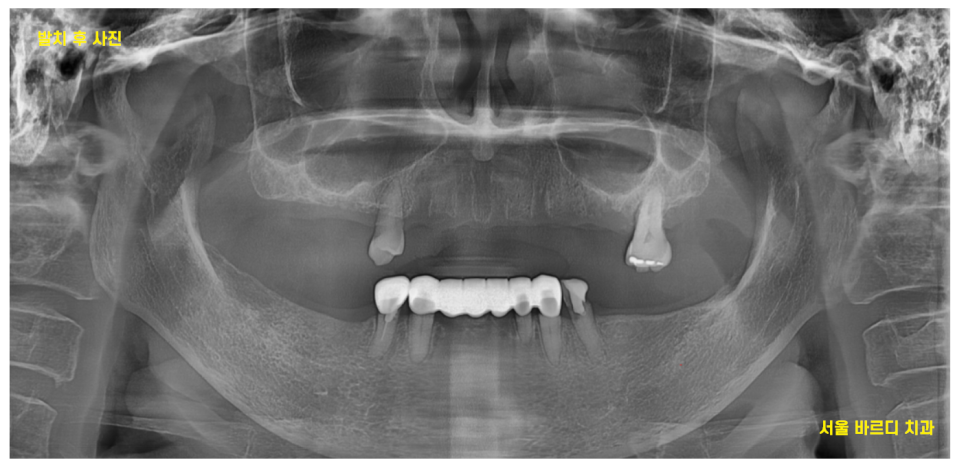

23.08.17

23.08.17 환자분을 처음 보았습니다.

어금니 치아는 위 아래 다 빠져있는 상황

남아 있는 치아 중에서도

문제가 많았습니다.

노랗게 삭아버렸거나

뿌리만 남아있는 치아도 많았는데요.

아래 치아의 경우 깨지고

치아가 뽑힌지 오래되어 잇몸뼈가 얼마 없는 상황이었습니다.

23.10.10

발치 후 치아의 모습이죠~?